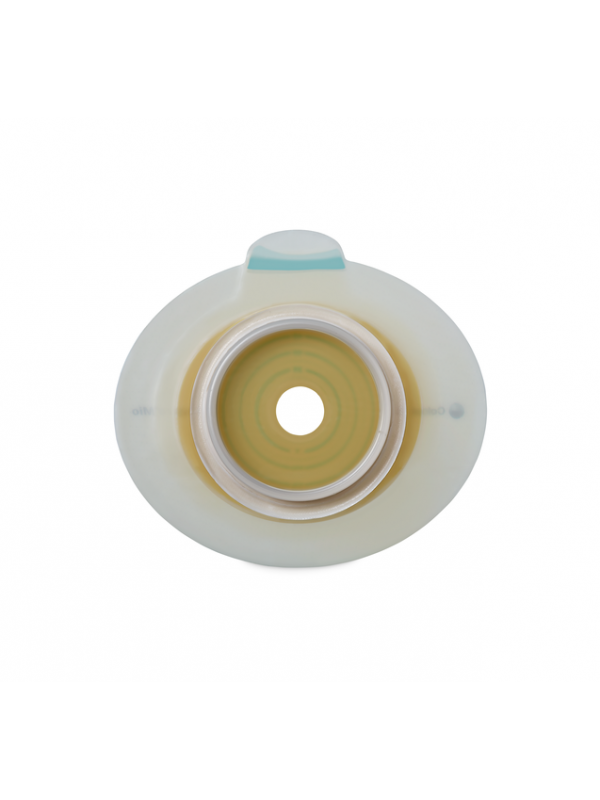

Płytka stomijna SenSura Mio dwuczęściowa – zaawansowane rozwiązanie dla użytkowników stomii

Płytka stomijna SenSura Mio dwuczęściowa to innowacyjny produkt, który łączy najnowsze technologie z wysokiej jakości materiałami, aby zapewnić użytkownikom maksymalny komfort, bezpieczeństwo oraz dyskrecję. Produkt został stworzony z myślą o różnych rodzajach stomii, takich jak ileostomia, kolostomia czy urostomia, i jest dedykowany osobom dorosłym. Dzięki swojej konstrukcji i elastycznym właściwościom płytka doskonale dopasowuje się do ciała, podążając za jego ruchami, co sprawia, że jej użytkowanie jest wygodne nawet w trakcie aktywności fizycznej.

System Click – pewne i łatwe mocowanie

Nowoczesny system Click to gwarancja bezpieczeństwa dzięki charakterystycznemu „kliknięciu”, które informuje użytkownika o poprawnym zamocowaniu worka na płytce. Dzięki temu rozwiązaniu wymiana worka stomijnego staje się szybka i wygodna, bez konieczności zdejmowania płytki.

Jak połączyć płytkę z workiem?

Proces łączenia płytki z workiem jest łatwy i intuicyjny dzięki zastosowaniu kolorowych oznaczeń. Kolory umieszczone na obu elementach wskazują ich kompatybilne rozmiary, co znacznie ułatwia dobór odpowiednich części, eliminuje pomyłki i przyspiesza codzienną obsługę systemu.

Dwuczęściowy system stomijny – komfort i niezawodność

System SenSura® Mio Click składa się z dwóch współpracujących elementów:

- Płytki stomijnej, która dzięki elastycznemu przylepcowi i solidnej konstrukcji idealnie dopasowuje się do kształtu ciała, zapewniając ochronę wrażliwej skóry wokół stomii.

- Worka stomijnego z trwałym mechanizmem zatrzaskowym, który umożliwia szybkie i bezpieczne połączenie z płytką, gwarantując stabilność i wygodę użytkowania.